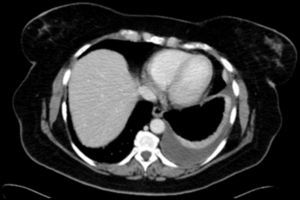

Cholesterol in the pleural space was thought to be due to erythrocyte and neutrophil degradation within a thickened pleura, but it seems more likely to originate from serum lipoproteins than from cell lysis.1 Pleural thickening with fibrotic scar tissue preventing fluid absorption was considered a key element in the etiopathogenesis of pseudochylothorax.1 However, in recent years, some cases of pseudochylothorax have been reported in patients with rheumatoid arthritis who have not shown pleural thickening, bringing the generally accepted pathogenic mechanism into question.4,5 We have diagnosed a new case of pseudochylothorax in a patient with rheumatoid arthritis who did not present pleural thickening. A 53-year-old woman, smoker (25 pack-years) with no previous respiratory symptoms, was referred to the respiratory medicine specialist after a small pleural effusion with no associated symptoms was detected on the study performed before an intervention for abdominal hernia. A chest radiograph obtained 7 months previously from the same patient did not show pleural effusion. She had been diagnosed with rheumatoid arthritis 2 years previously and was receiving treatment with corticosteroids, methotrexate and certolizumab. On chest CT (Fig. 1) pleural effusion was observed with no signs of pleural thickening. A thoracocentesis was performed, yielding a sterile, opalescent fluid with no malignant cells, pH 7.03, glucose <20mg/dl, proteins 7g/dl, LDH 14,691U/l, ADA 137U/l, rheumatoid factor <9U/ml, triglycerides 17mg/dl and cholesterol 255mg/dl (in serum 186mg/dl).